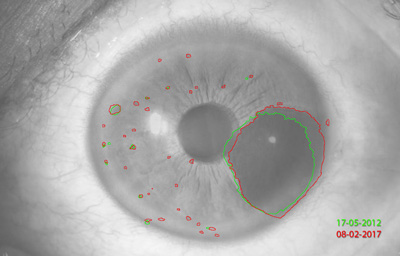

Melanocitomas

Melanocitoma es una lesión benigna, profundamente pigmentada, variante del, nevus uveal que fue originalmente descrito por Zimmerman y Garron en 1962 en el nervio óptico; ahora se sabe que puede aparecer en cualquier lugar del tracto uveal.

Son masas con algo de elevación, con pigmento marrón oscuro casi negro, frecuentemente con apariencia de “ montículo de arena negra”. Sus células son ovoides con núcleos uniformes, pequeños y muy pigmentados. pueden generar satélites en el estroma o en el ángulo de la cámara anterior. Pueden evolucionar a Melanoma (30)

Aniridia

Archivo Fotográfico Dr. Francisco Barraquer. 2012

Nevus con escaso pigmento

Archivo Fotográfico Dr. Francisco Barraquer. 2017

Estudio comparativo